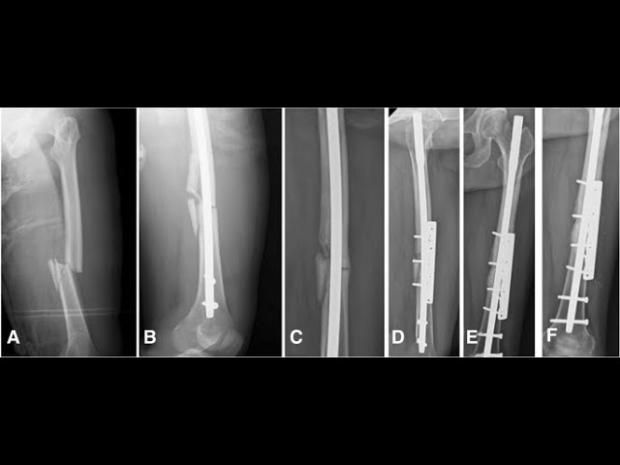

في واحدةٍ من أكثر الإصابات قسوة هذا الموسم، تعرض اللاعب الجزائري أحمد القندوسي، المعار من النادي الأهلي إلى سيراميكا كليوباترا، إلى كسرٍ مضاعف في الساق خلال مباراة أمام نادي فاركو، ليُصاب الذهول في المدرجات والصمت في المستطيل الأخضر، وكانت الإصابة عنيفة لدرجة أنها استدعت تدخلًا جراحيًا عاجلًا لتركيب مسمار نخاعي داخلي لتثبيت العظام، وهي من العمليات الدقيقة التي تُستخدم غالبًا في الحالات المعقّدة.

وأضاف علام أنّ التقييم المستمر باستخدام الأشعة هو الفيصل في تحديد مدى تقدم الالتئام، مشيرًا إلى أن أي استعجال في زيادة الأحمال قد يؤدي إلى مضاعفات خطيرة، أو تأخر التئام العظام، وهو ما يمثل كابوسًا لأي لاعب محترف.

ويُبنى برنامج التأهيل خطوة بخطوة، بحيث تنتقل التمارين من مستوى ثابت إلى تمارين مقاومة، ثم تمارين ديناميكية تشمل التوازن والتحكم، ومع مرور الوقت يتم إدخال تدريبات الركض والمناورات الخاصة باللعبة.